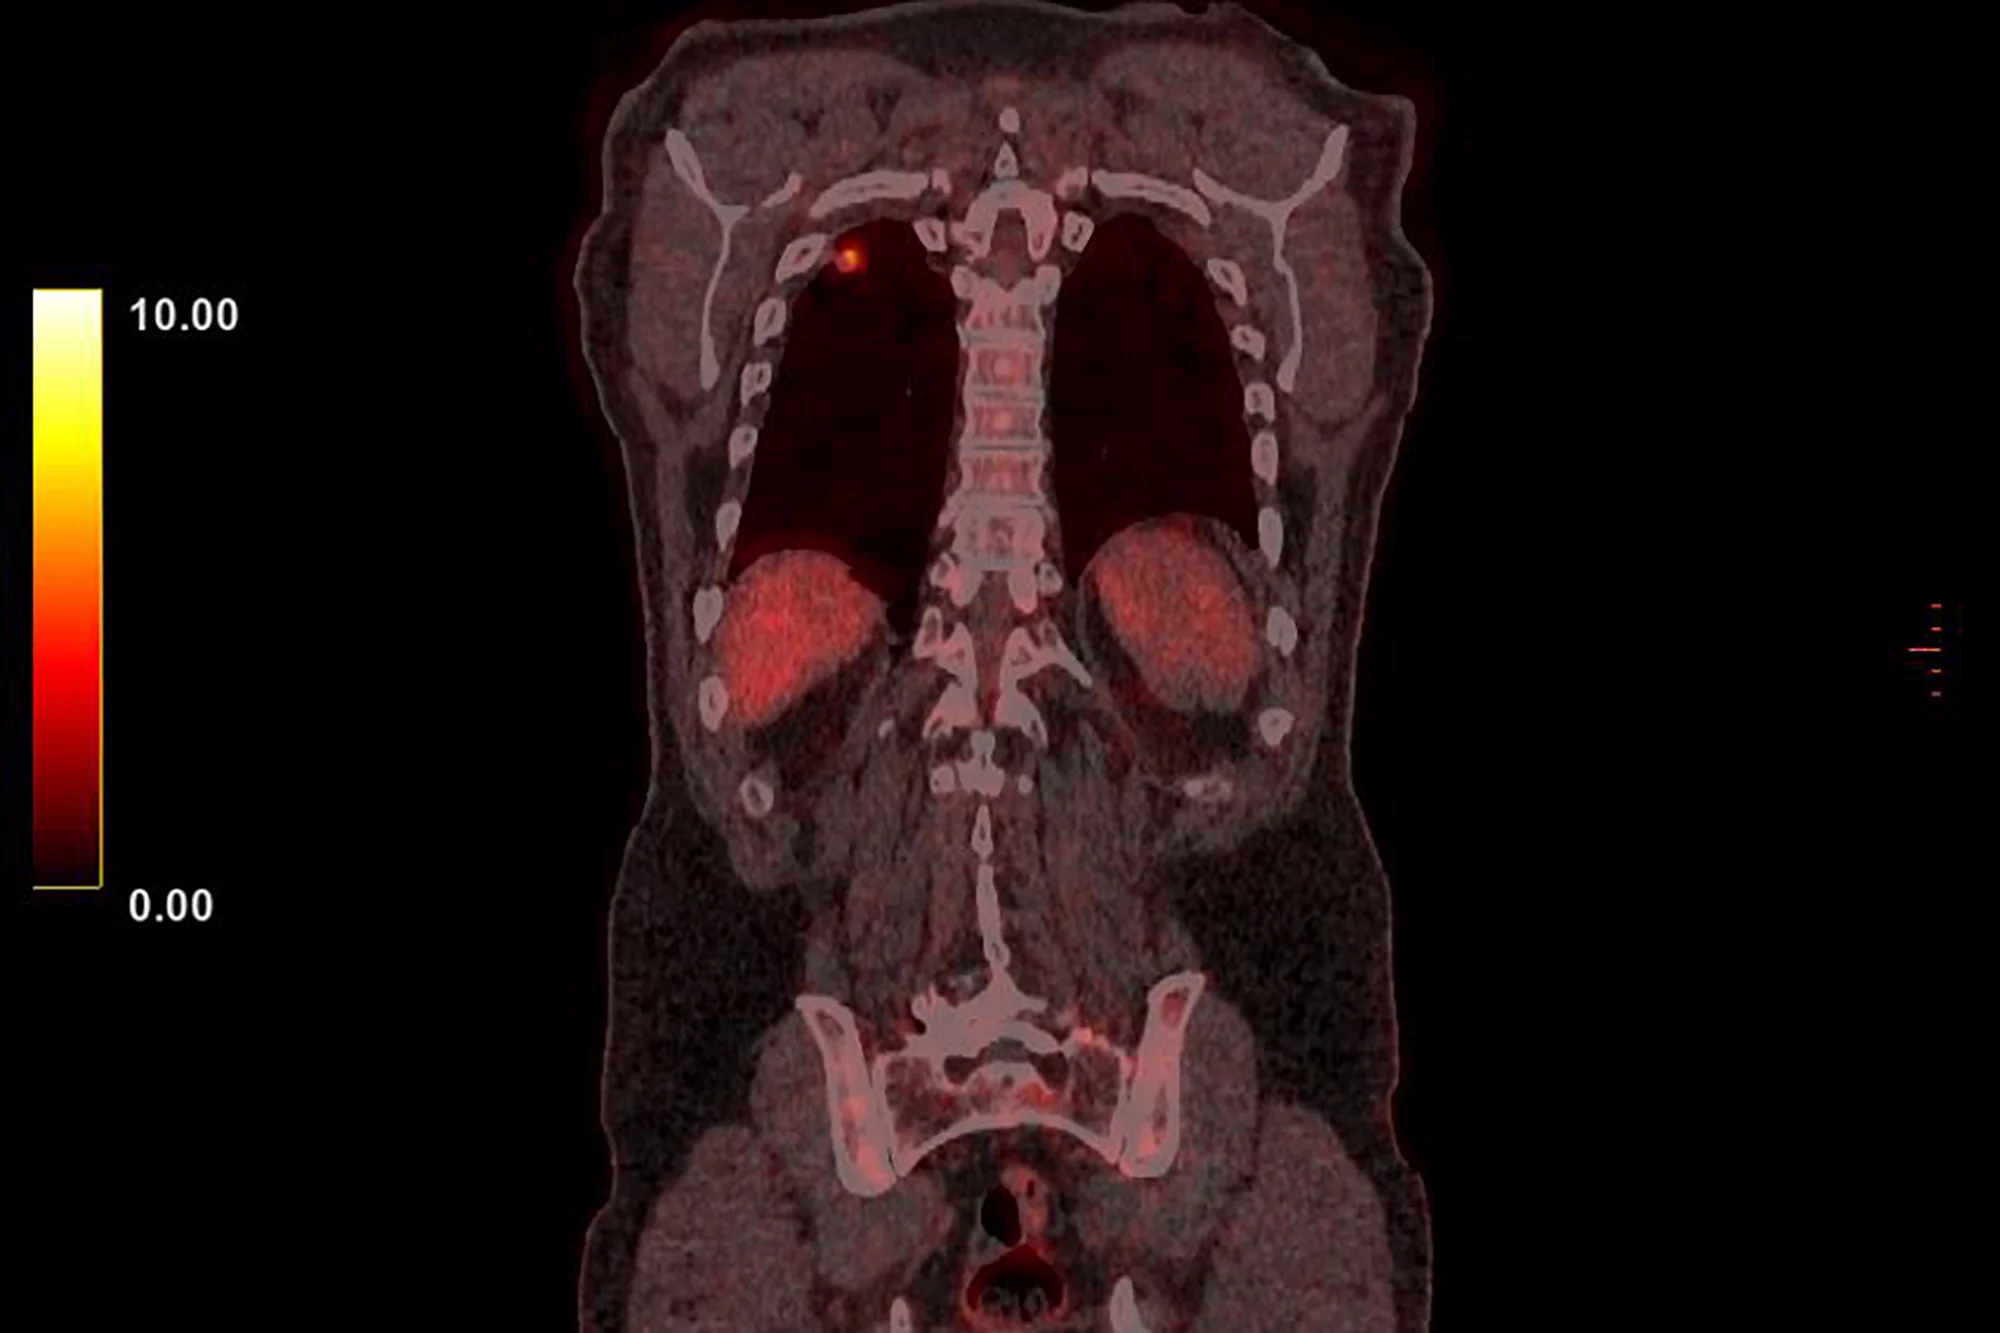

Immunotherapy drug tarlatamab has produced promising results in people with deadly small cell lung cancer for whom previous treatment hasn't worked